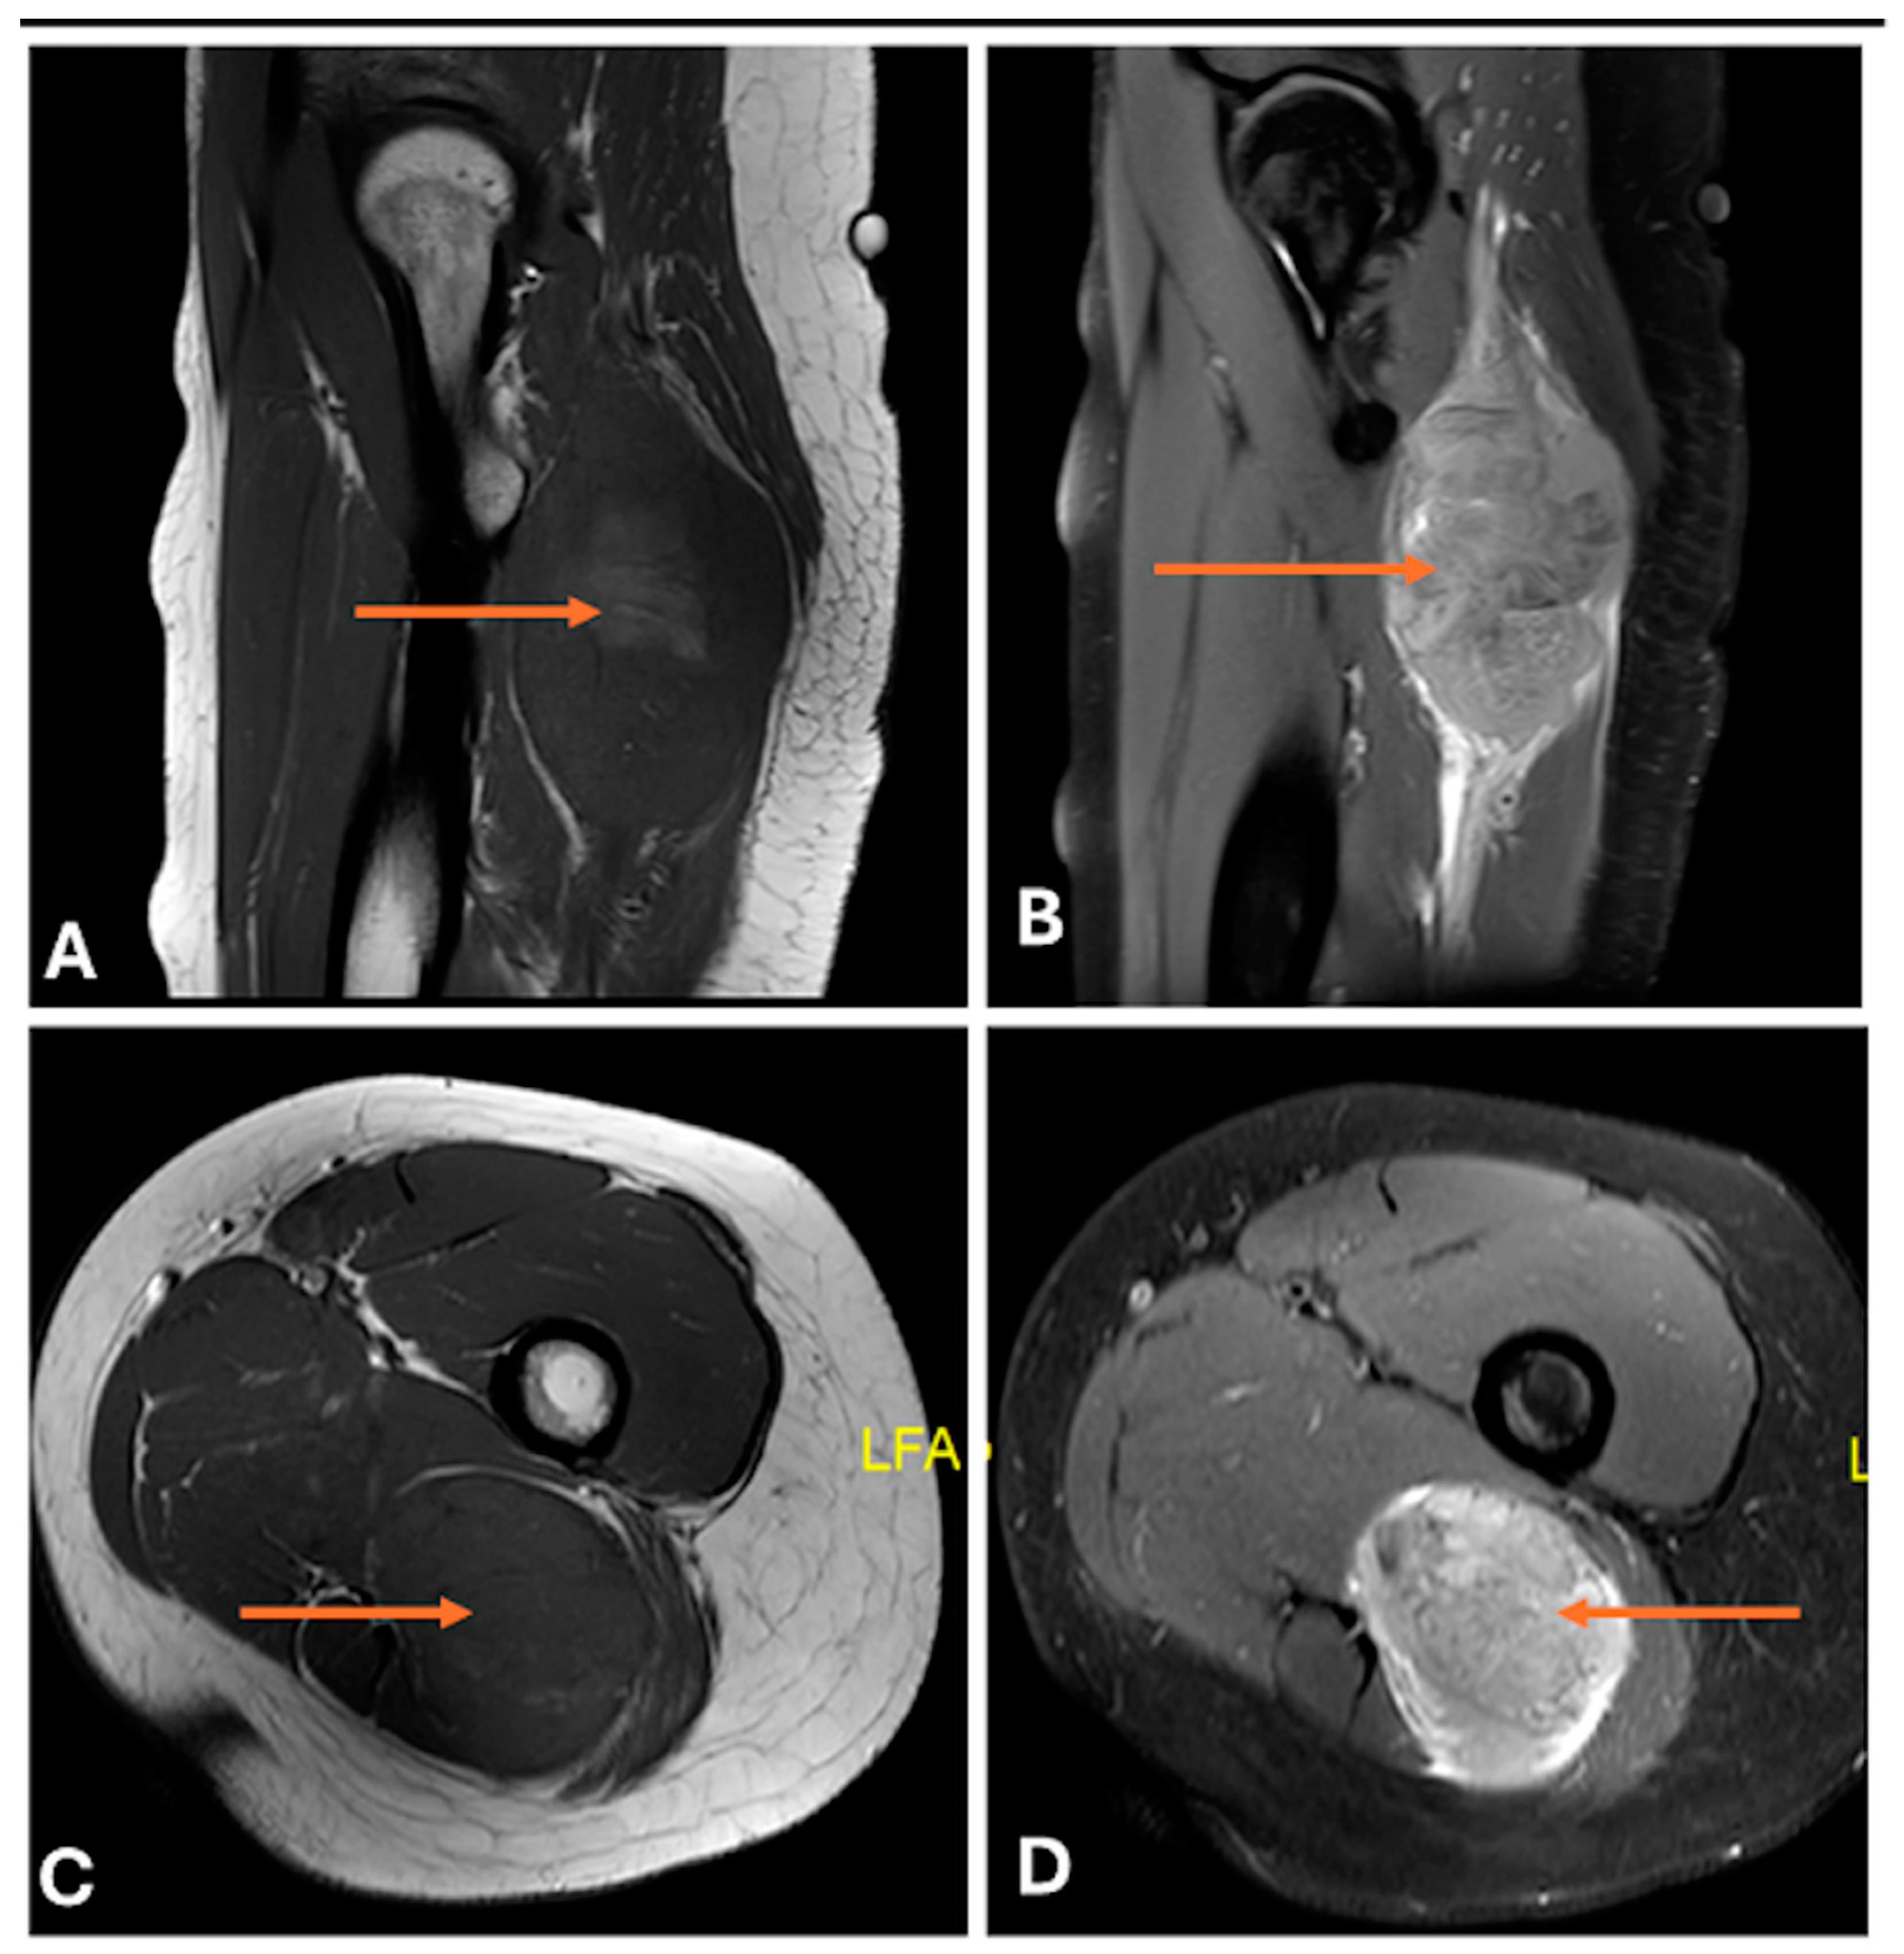

- Primary Sarcomas: Soft-tissue sarcomas are uncommon, accounting for just over 1% of adult malignancies. Synovial sarcoma, clear cell sarcoma, and epithelioid sarcomas are known to involve peripheral nerves. CT/MR reveals a large soft tissue mass with areas of necrosis or calcification and heterogeneous contrast enhancement. F-18 FDG uptake is useful for both tumor staging and treatment assessment (Figure 26, Figure 27 and Figure 28).